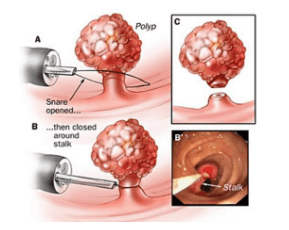

Trong kĩ thuật cắt niêm mạc qua nội soi (EMR – Endoscopic Mucosal Resection), được sử dụng để cắt các polyp không cuống, một lượng dung dịch được tiêm vào lớp dưới niêm để nâng tổn thương ở lớp niêm mạc ra khỏi lớp dưới niêm, điều này giúp tránh biến chứng thủng ống tiêu hóa trong thủ thuật.

Tuy nhiên, nếu đã tiêm một lượng dung dịch, nhưng không nâng được tổn thương lên, thì rất có thể tổn thương polyp đã xâm lấn hoặc xơ hoá xuống lớp dưới niêm. Những trường hợp như vậy, hãy cẩn thận, vì có thể đây là polyp ung thư hoá.

Ưu điểm của các máy nội soi là có dải tần ánh sáng hẹp (NBI), hình ảnh nội soi NBI có độ phân giải và độ tương phản cao nên dễ dàng hơn phát hiện và sàng lọc và chẩn đoán ung thư tiêu hóa ở giai đoạn sớm. Một khi tổn thương ung thư được phát hiện ở giai đoạn sớm, tùy theo tính chất polyp, sẽ được cắt theo phương pháp cắt niêm mạc (EMR), hoặc cắt bóc tách dưới niêm mạc (ESD) qua nội soi ống mềm, mà không phải trải qua phẫu thuật.